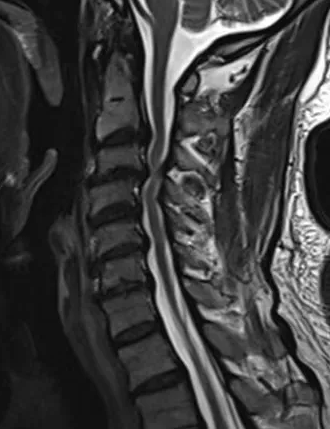

患者为一名中老年男性,近半年来反复出现双下肢麻木、沉重感,行走时如同“踩在棉花上”,病情逐渐加重,严重影响日常起居。经多方打听,患者慕名来到西安市中心医院经开院区骨科就诊。接诊医生详细询问病史并进行全面查体后,结合颈椎MRI检查,明确诊断该患者为脊髓型颈椎病,颈椎间盘突出组织已明显压迫脊髓,保守治疗效果有限,需尽快手术解除压迫,否则可能导致肢体功能不可逆损伤,甚至瘫痪。

脊髓型颈椎病是危害最严重的一类颈椎病,其病变进展隐匿但后果严重,早期常表现为肢体麻木、步态异常,晚期可出现瘫痪、二便功能障碍等并发症。针对患者病情,骨科团队展开了缜密的术前讨论。考虑到传统开放手术创伤较大、恢复周期长,加之患者年龄偏大,对手术耐受性有一定要求,团队最终讨论确定采用国际公认的颈椎病手术“金标准”——颈椎前路椎间盘切除融合术(ACDF)为患者治疗。该术式通过颈部前方微小切口,精准切除病变椎间盘及骨赘,解除脊髓与神经根压迫,同时植入融合器并进行内固定,重建颈椎稳定性,具有创伤小、减压确切、恢复快等显著优势。